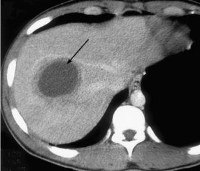

A06.4 Амебный абсцесс печени